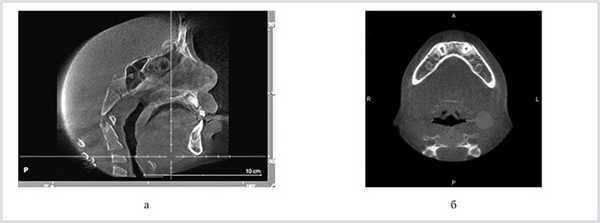

КЛКТ-исследование осуществлялось на конусно-лучевом томографе New Tom 3G («Q&R», Италия) до и после ортодонтического лечения. Измеряли параметры носоглотки, оценивали степень гипертрофии носоглоточных миндалин. Визуализацию трехмерного изображения выполняли с помощью программы Amira. После реконструкции изображений с толщиной среза 0,4 мм формировались реформатированные изображения в аксиальной и сагиттальной проекциях (рис. 2). Определение переднезаднего размера ротоглотки проводилось на срединно-сагиттальном срезе.

Рис. 2. КЛКТ. Результатуты конусно-лицевой компьютерной томографии. а — срединно-сагиттальный верхний и нижний ротоглоточные размеры; б — аксиальный срез, определение переднезаднего и трансверсального размеров ротоглотки.